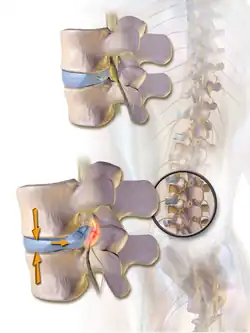

Schéma d'une vue latérale gauche du rachis montrant une hernie discale lombaire postérolatérale gauche avec compression d'une racine nerveuse.

La hernie discale résulte habituellement de la progression d'une protrusion discale, c'est-à-dire une lésion incomplète de l'anneau fibreux permettant une saillie intermittente, selon les contraintes exercées sur le disque. Cette saillie est permanente lorsque survient la hernie.

La hernie postérieure est favorisée par la compression de la portion antérieure du disque lors de la flexion antérieure du tronc, ce qui entraîne la poussée du noyau pulpeux contre la portion postérieure de l'anneau fibreux. Ceci peut aboutir à la rupture de l'anneau fibreux et au déplacement progressif du contenu du noyau pulpeux à travers cette lésion vers le canal vertébral. La compression d'un nerf spinal du fait d'une hernie entraîne des symptômes décrits plus bas.